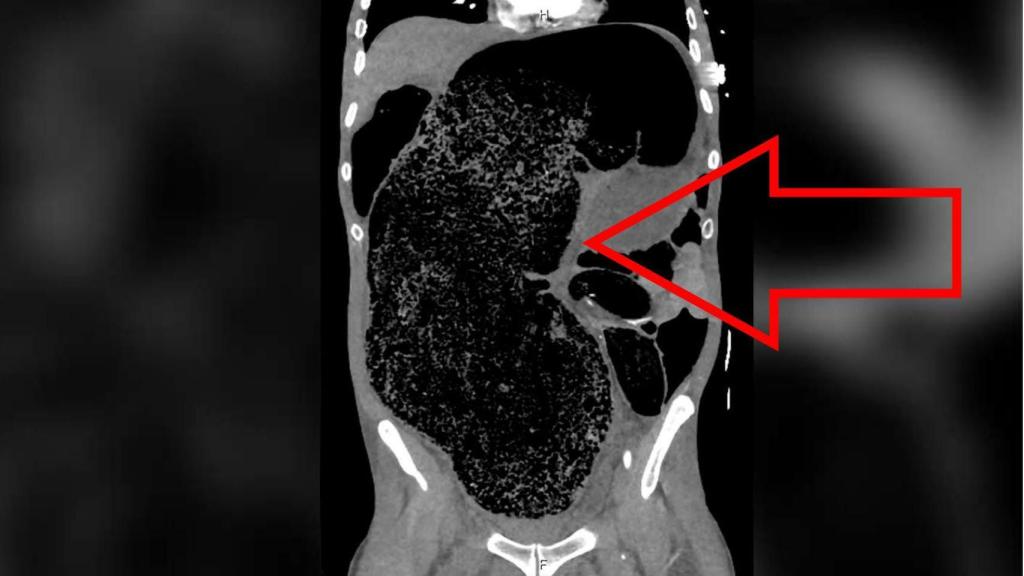

Imagen por escáner de la impactación fecal masiva que sufría el paciente en su abdomen. BMJ Case Reports

Lo que vemos en la imagen del interior del cuerpo del paciente que ilustra este artículo no es un órgano inflamado, el crecimiento de un tumor masivo o un cuerpo extraño a su propio organismo. Es caca. Por motivos que no han trascendido, este australiano de 57 años llevaba días sin ir al baño. Pero no acudió finalmente al médico hasta que se presentó un síntoma alarmante: había perdido el uso de la pierna derecha.

El paciente no tenía un historial de enfermedades cardiovasculares ni de medicación o consumo de estupefacientes que justificasen el diagnóstico de isquemia, el corte del riego sanguíneo que proporciona la arteria a la pierna. Fue el escáner abdominal lo que reveló un caso extremo de impactación fecal, la situación en la que las heces retenidas se endurecen y secan en el interior del organismo, formando una gran masa.

En este caso, la compactación había llegado al punto de provocar la distensión de su intestino grueso y abdomen, y la enorme masa impactada presionaba contra su arteria ilíaca derecha, provocando la isquemia responsable de cortar el riego a su pierna. También sufría síntomas de fallo renal y acidosis metabólica -una acumulación perniciosa de ácido- que determinaron una intervención quirúrgica inmediata.